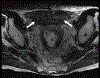

Objective: The purpose of this article is to review the etiopathogenesis, molecular cytogenetics, histopathology, clinical features, and multimodality imaging features of desmoid fibromatosis. Recent advances in the management of desmoid fibromatosis will also be discussed.

Conclusions: Desmoid fibromatosis is a rare soft tissue neoplasm with a high incidence of local recurrence. Imaging plays an important role in the diagnosis and management of this disease.